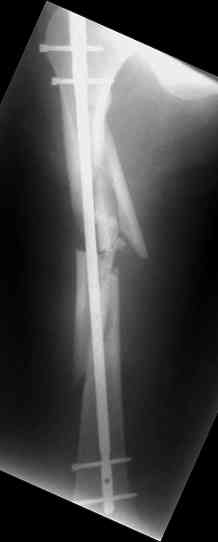

молодй человек 26лет получил С3-перелом правого бедра и легкую черепно мозговую травму (сотрясение головного мозга). Через неделю (противошоковые мереприятия и скелетное вытяжение выполнялось в ЦРБ)оперирован: БИОС бедра стержнем СнМ, Польша. Выписан со швами на амбулаторное лечение по месту жительства в г. Ижевск.Через 1месяц главным врачом больницы, со слов пациента, предложен реостеосинтез пластиной "соберем кость".

Надеюсь сейчас показать перелом, а потом синтез.

Про "кролика", конечно, не очень хорошо с точки зрения деонтологии. Но коллега, Вы думаете кто-нибудь из заядлых Nailer- ов оценит положительно этот остеосинтез? Возможно, на то были объективные причины: отсутствие штифтов большего диаметра..., штифтов, позволяющих блокировать более толстыми винтами..? А уж Plater-ы, конечено засмеют.

У данного пациента есть все основания ожидать несращения. Менять штифт (безусловно тонкий и недостаточно стабильный для этого перелома) на пластину не лучший вариант, особенно, если предполагается открытая операция. Или главный врач в Ижевске имеет ввиду длинную мостовидную пластину LCP по технике MIPO? Тогда шансов на сращение будет больше, чем сейчас, но с нагрузкой придется очень и очень подождать.

Мы бы сейчас перештифтовали : удалить, рассверлить, и забить штифт 13-16 мм диаметром и на пару см. подлиннее. Предпочтительнее штифт, имеющий изгиб во фронтальной плоскости в проксимальном отделе для введения через верхушку б\вертела и имеюший возможность проксимального блокирования по оси шейки бедра.